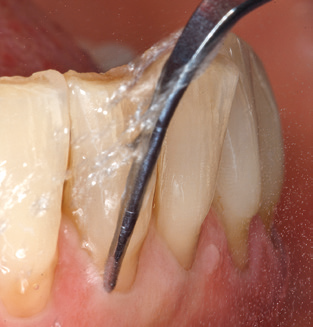

Good illumination of the working field facilitates the process considerably. The system used by the authors achieves this thanks to a 5x LED ring integrated in the handpiece. Naturally, a range of working tips for different indications is also offered. A straight, universally employable tip is the basic instrument required for machine cleaning of natural teeth (Fig. 5a and b). Curved tips, which allow access to exposed furcations, are also available for hard-to-reach areas in the posterior region (Fig. 6).

Following machine cleaning of the tooth and implant surfaces, the surfaces of the natural teeth are cleaned manually using standard hand instruments. When performing manual cleaning, particular attention must be given to maintaining the correct angle of application, appropriate sharpness, good support and working with the curette from apical to coronal. Either titanium or carbon curettes should be used for post-cleaning of the implant structures (Fig. 8). In addition to the use of ultrasonic devices, power jet devices can also be used in conservative dentistry. However, it must be taken into consideration that these procedures are not suitable for removing hard deposits and thus they cannot replace the use of hand instruments and ultrasonic instruments completely. In all cases, cleaning is followed by mechanical polishing of the accessible tooth and implant surfaces with polishing cups and polishing compounds (Fig. 9).